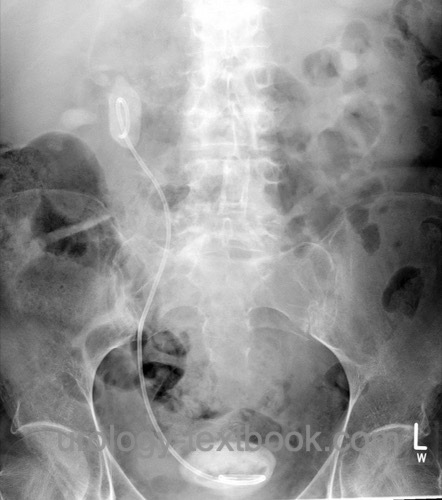

Incrustation:

Biofilm leads to encrustation and obstruction. Forgotten stents may be encased in massive stone formations, making removal difficult [Fig. Forgotten DJ stent].

![]() |